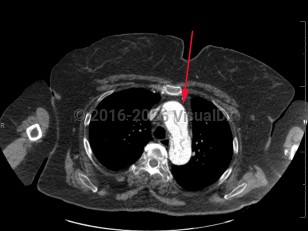

Low back pain, Abdominal cramp, 50-59 year old Female